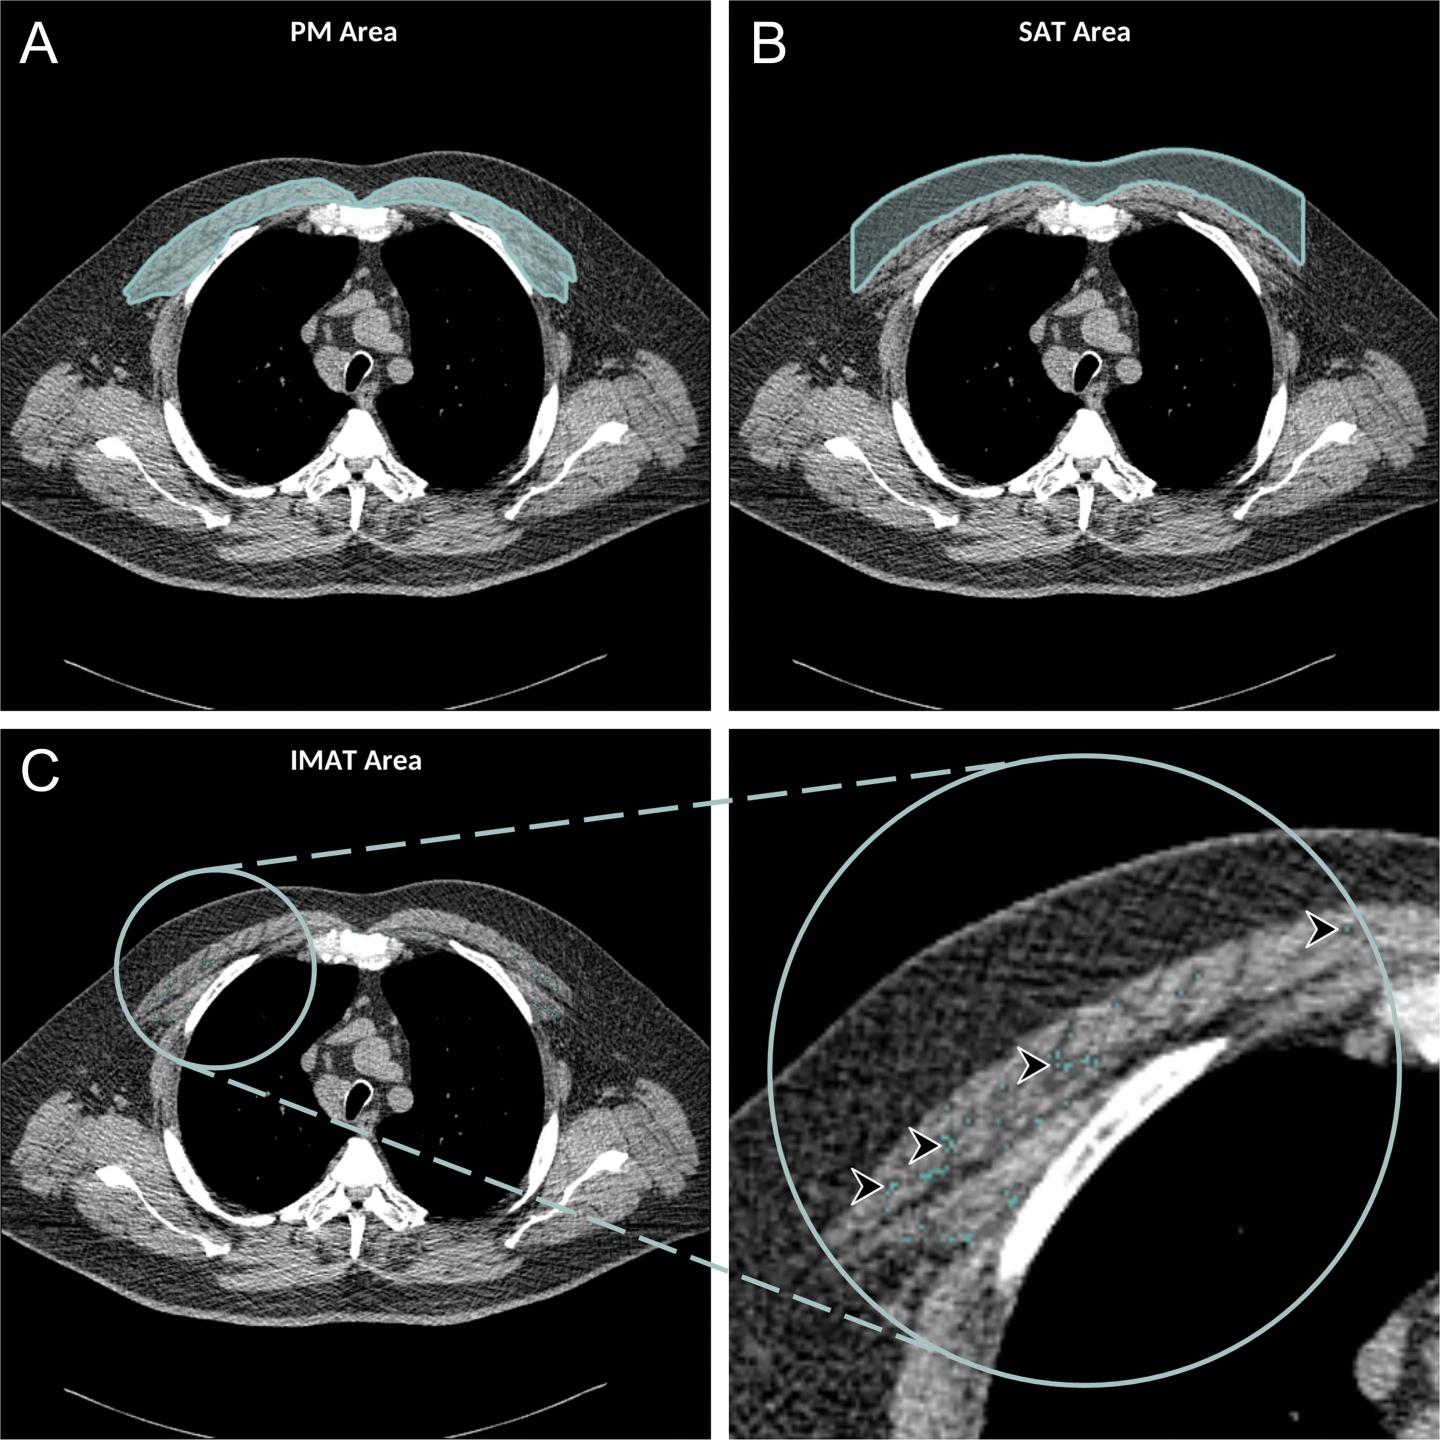

image: Axial chest CT examination in a 54-year-old participant. A, On the axial noncontrast chest CT image, the pectoralis muscle (PM) area was segmented and measured in the section above the aortic arch. B, The subcutaneous adipose tissue (SAT) area as the area between the PM and the skin surface on the same section was also measured and the attenuation of pixels in the SAT area was used to determine the individualized threshold for the intermuscular adipose tissue (IMAT). C, The IMAT within the PM was segmented as the areas with Hounsfield units below this threshold for the IMAT (arrowheads).

A greater amount of intermuscular fat was associated with higher mortality rates. Existing research has linked higher levels of intermuscular fat with diabetes and insulin resistance.

Higher subcutaneous adipose tissue, in contrast, was linked to lower risks of all-cause mortality.